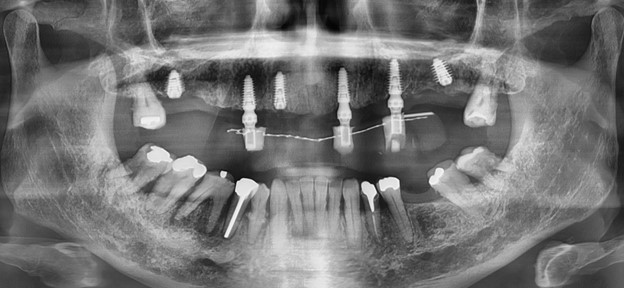

Phim X-Quang cho thấy có nhiều vùng nhiễm trùng ở hàm trên và dưới

X-Quang ngay sau gắn răng tạm cố định

X-Quang sau khi gắn phục hình chính thức

Tái khám sau 22 tháng mang phục hình sau cùng – xương ổn định, không có hiện tượng viêm hay tiêu xương